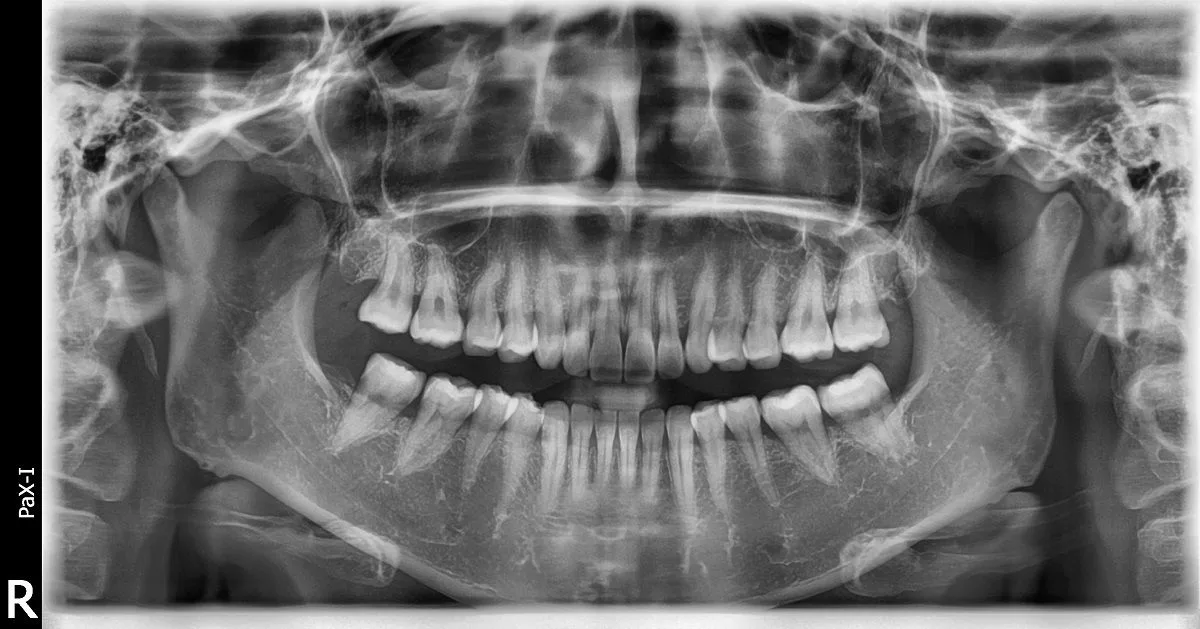

Standardowa diagnostyka obrazowa w stomatologii opiera się na zdjęciu pantomograficznym (OPG) i zdjęciach celowanych (periapikalnych). Oba badania są płaskie – projicują trójwymiarową strukturę zęba na dwuwymiarową kliszę lub sensor cyfrowy. Zachodzące na siebie struktury anatomiczne, skrzywienie korzenia w płaszczyźnie niewidocznej dla prześwietlenia, zmiany periapikalne o małej gęstości lub torbiel rozwijająca się wolno bez wyraźnej destrukcji korowej – wszystko to może pozostawać niewidoczne przez wiele wizyt na diagnostyce 2D.

OPG i zdjęcia celowane pozostają pierwszą linią diagnostyki – szybkie, tanie, niskonakładowe. CBCT zlecane jest wtedy, gdy dane 2D są niewystarczające do podjęcia decyzji klinicznej. Zakres i wskazania do badania zawsze ustala lekarz.

Zdjęcie RTG celowane (periapikalne) to płaska projekcja 2D – projicuje trójwymiarową strukturę zęba na dwuwymiarowy obraz, przez co struktury leżące przed i za sobą nakładają się. CBCT zębów rejestruje wybrany ząb lub sektor w trójwymiarze: lekarz ogląda go w trzech prostopadłych przekrojach jednocześnie, bez nakładania się struktur. Widoczna jest rzeczywista liczba kanałów, skrzywienia w obu płaszczyznach, zasięg zmiany periapikalnej w milimetrach i relacja do kanału nerwowego lub dna zatoki. Te dane są fizycznie nieobecne na projekcji 2D – nie chodzi o wyższą rozdzielczość tego samego obrazu, lecz o inny wymiar informacji. Zdjęcie celowane pozostaje pierwszym badaniem z wyboru ze względu na minimalną dawkę i koszt; CBCT zlecane jest, gdy dane 2D nie wystarczają do decyzji klinicznej.

RTG zębów – OPG panoramiczne

Zdjęcie panoramiczne jako pierwsza linia diagnostyki obrazowej – szybki przegląd uzębienia i kości; uzupełniane CBCT small FOV gdy obraz 2D nie dostarcza danych wystarczających do decyzji.